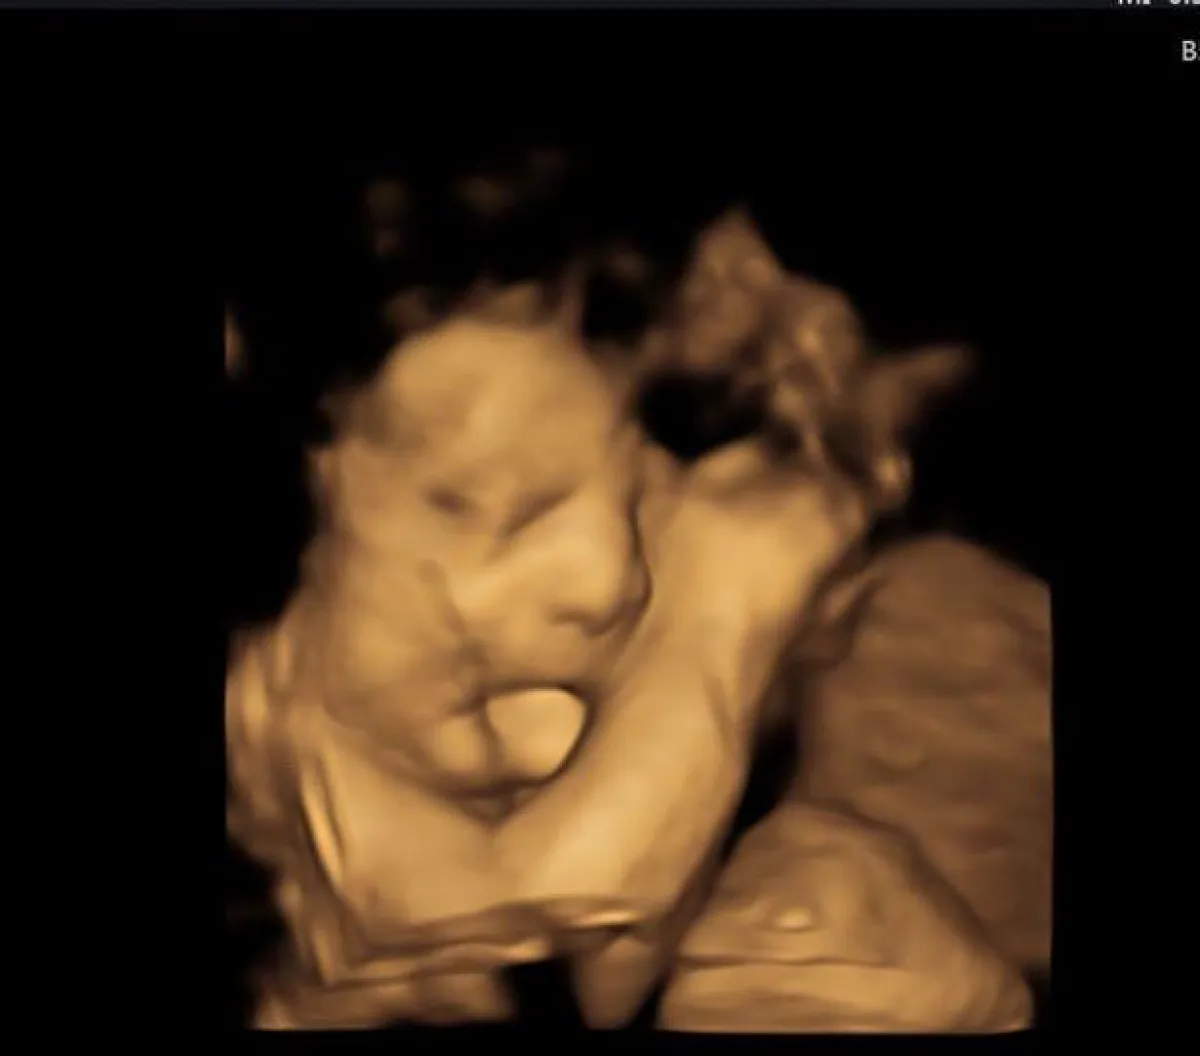

واعتقدت والدته فرح روث، من جينكس أوكلاهوما، في البداية أنه شيء طبيعي، وفي فحوصات الموجات فوق الصوتية لم يلتفت الطبيب أثناءالحمل لهذه المسألة، إذ إن ليس كثير من الأطباء على دراية بهذه المتلازمة، ولكن من الناحية الواقعية، كانت هذه النتوءات الكبيرة تسببها BWS، وبعد العملية وإزالة نصف لسانه، أصبحت ابتسامته ألطف بكثير مما كان عليه، وأصبح قادراً على تناول أطعمة أكبر الآن، مثل البسكويت أو الهامبرجر المقطع، والذي يضعه في فمه بنفسه، كما أنه بدأ يتعلم كيف يشرب ويأكل ويتواصل بشكل صحيح، هو يستخدم اللغة حاليًا أكثر للتواصل ويحاول المشي.